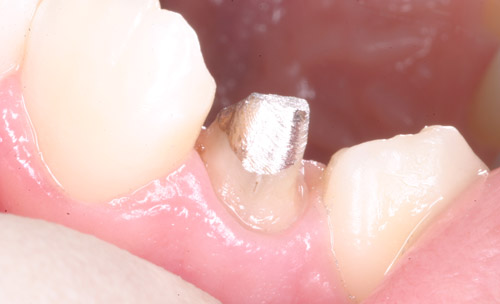

ファイバーコア

メタルコア

治療後